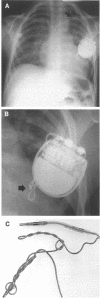

Mechanical causes of pacemaker failure are well recognised. Twiddler's syndrome leading to pacemaker failure has been previously recognised in adults, but there have been no published reports of its occurring in children. Two cases leading to failure of the pacing system are reported. In the first twiddling led to fracture of the lead and in the second it led to displacement of the lead from the heart. Children may be more susceptible to twiddler's syndrome because they have thinner subcutaneous tissues, making leads more accessible, and their comprehension of the consequences may be poor.